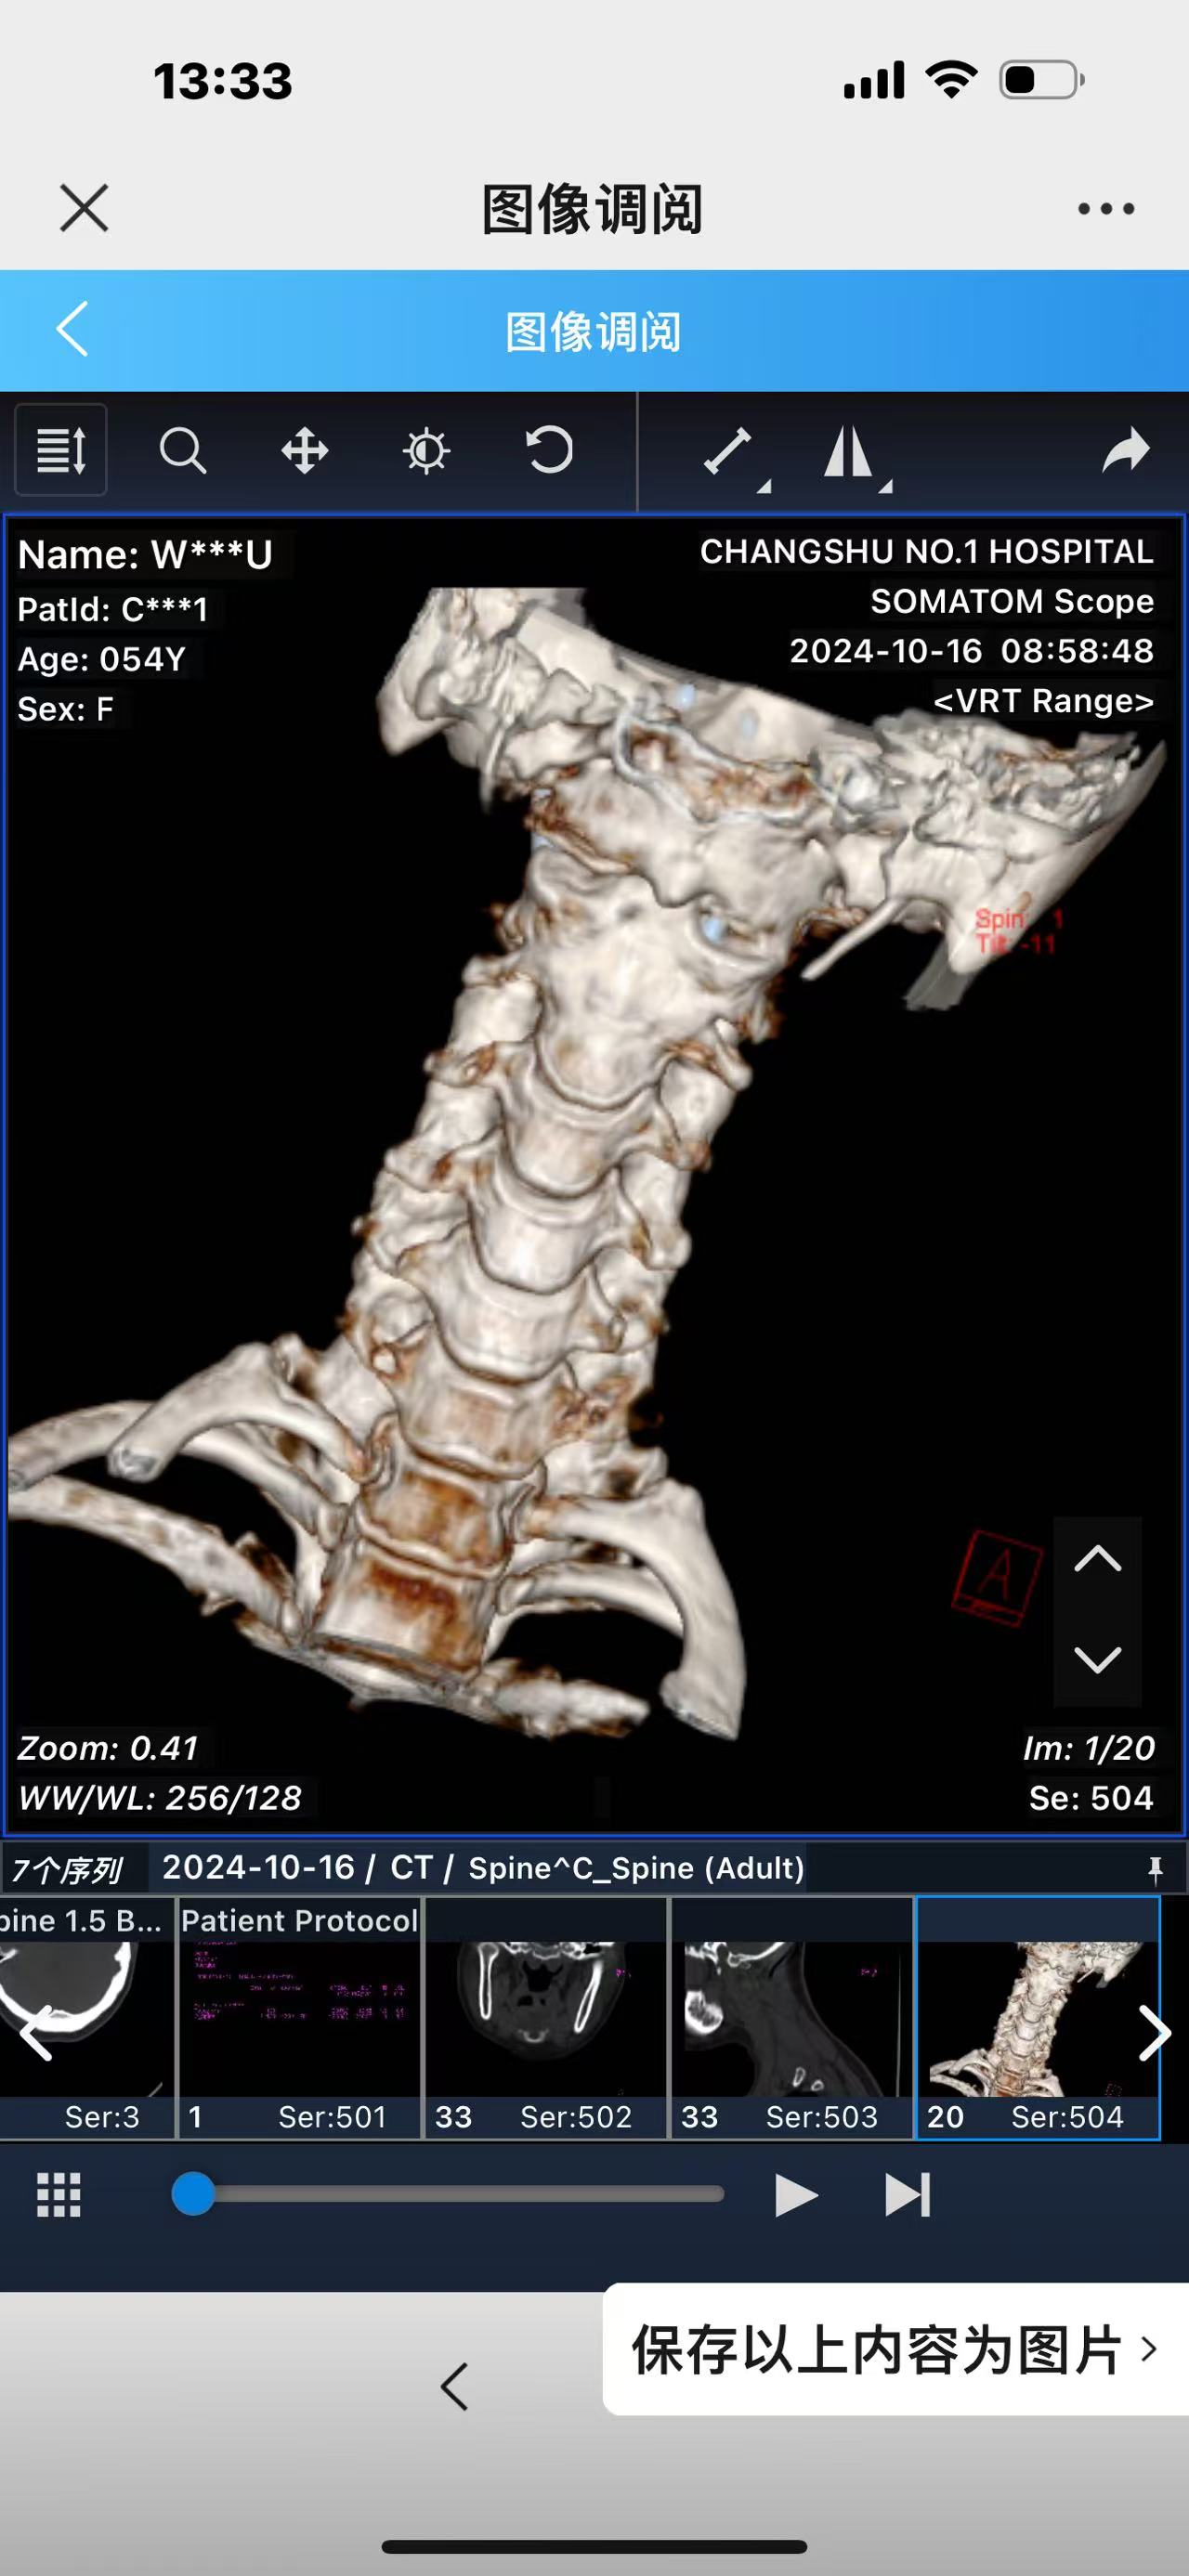

• 诊断:寰枢椎脱位,颅底凹陷

• 术后影像:

• 2024.10.20,复查,对位良好,偶尔会肩甲骨酸,坐下就不酸。